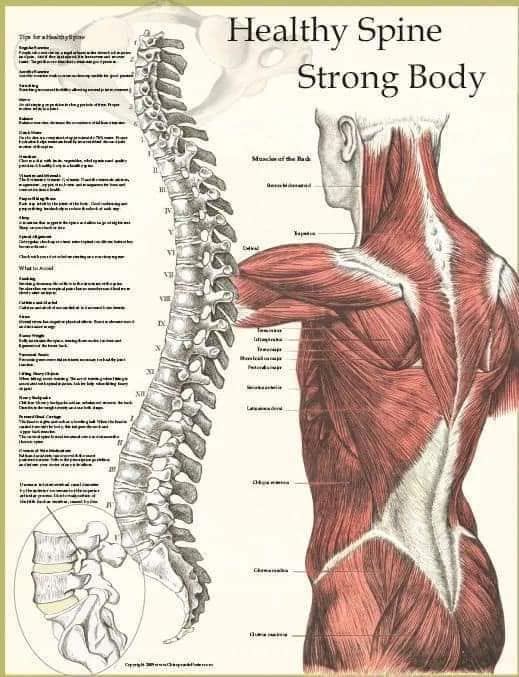

Спинні м'язи виконують функції підтримки хребта, а також дозволяють здійснювати рухи тулуба.

Поверхневі спинні м'язи

М'язи, що піднімають лопатку: Трапецієподібний м'яз: великий м'яз, що покриває верхню частину спини. Його функція - підтримка і рух лопаток, а також забезпечення стабільності хребта.

М'язи, що ведуть лопатку до хребта: Широкий м'яз спини: великий м'яз, що розташований в нижній частині спини. Він відповідає за рухи плечей і лопаток, а також за розширення верхньої частини тулуба.

Глибинні спинні м'язи

М'язи, що забезпечують стабільність хребта: М'язи, що розташовані між хребцями: включають мускулатуру, яка забезпечує стабільність і підтримку хребта, а також дозволяє здійснювати рухи хребта.

М'язи, що здійснюють ротацію та нахили

М'язи, що забезпечують ротацію хребта: Ротаційні м'язи: допомагають у здійсненні обертальних рухів тулуба, а також у підтримці рівноваги і стабільності хребта.